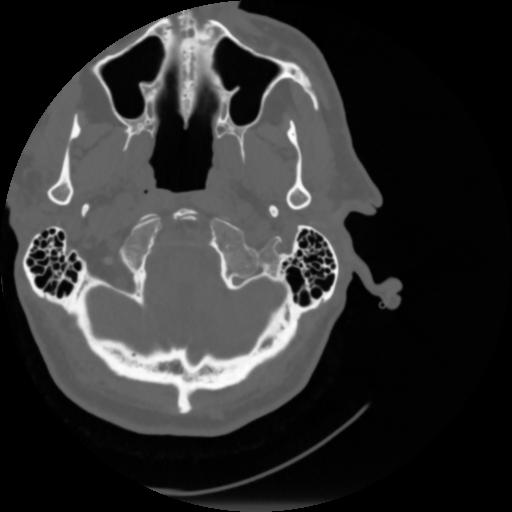

4 CEREBRO,,Vol,0.5,CEREBRO,,